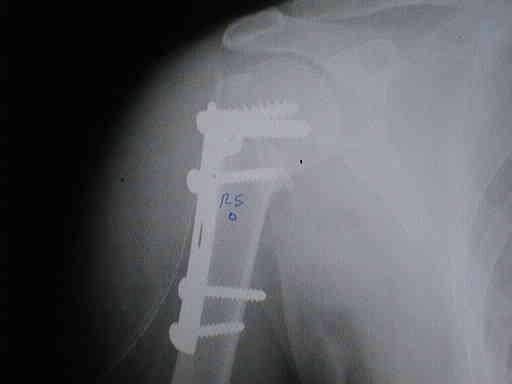

POST-OPERATORIO

POST – OPERATORIO